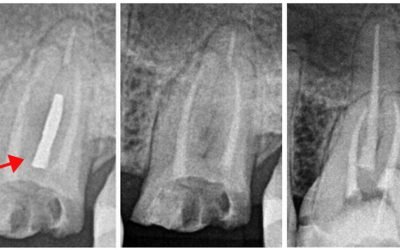

Remoção de Lima Fraturada

Existem várias técnicas para remoção de instrumentos fraturados no canal e é bom que o Endodontista conheça todas elas, pois a cada caso uma determinada técnica pode funcionar em detrimento das outras. Para a remoção de lima fraturada ou qualquer...